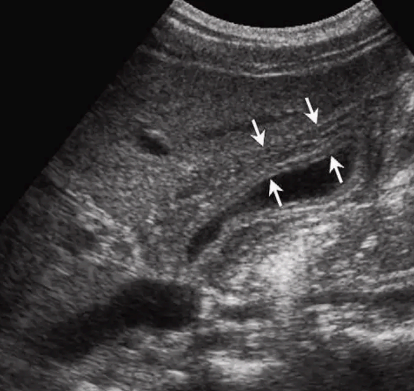

US finding

- 담낭주위 띠모양의 경계가 좋은 액체저류가 보인다

- 담낭은 경계가 불분명해지며 팽팽해진다

- 심한 경우 저에코성 종괴들이 관찰된다